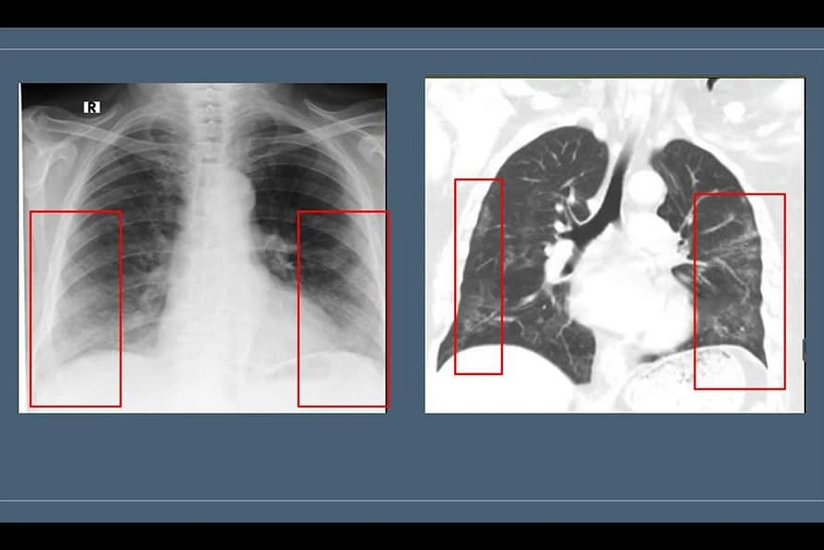

Həkimin sözlərinə görə, bəzən normal hallarda da “buzlu şüşə” görüntüsü radioloji görüntülərdə izlənilə bilər: "Məsələn, müayinə zamanı xəstə dərindən nəfəs almazsa və ya müayinə nəfəsvermədə aparılarsa, ağciyərin havalılığının fizioloji ekspirator zəifləməsi səbəbindən bütün ağciyər sahələri homogen olmaqla “buzlu şüşə” görüntüsü verə bilər. Hazırda “buzlu şüşə” görüntüsü koronavirus pnevmoniyasının əsas radiodiaqnostik əlaməti hesab edilir. Bu o deməkdir ki, normalda şəffaf havalı görünən ağciyərdə belə hallarda yarımşəffaf zonalar izlənilir, ağciyər sanki dumanlı görünür. Bu zaman bronx strukturlarının və pulmonar damarların saxlanması ilə ağciyərlərin eksudat və ya transudatla tutulması, interstisial qalınlaşmalar və ağciyər alveollarının hissəvi kollapsı ilə müşahidə olunan görüntü meydana çıxır. Buzlu şüşə xəstəliyin 3-4 günlərindən inkişaf etməyə başlayır və xəstə sağaldıqdan hətta bir ay sonra belə qala bilir. Xəstəliyin yüngül və orta ağır dərəcəsini keçirmiş xəstələrdə 2-3 aydan sonra dəyişikliklər tamamilə itir”.

Radioloq qeyd edib ki, indi onlara ən çox verilən sual “buzlu şüşə” görüntüsünün indiyədək mövcud olub-olmaması ilə bağlıdır. "Bu, yalnız COVID-19 xəstələri üçün səciyyəvi deyil, digər xəstəliklərdə də görülə bilər. Lakin bu görüntü pandemiya dönəmində uyğun kliniki-laborator əlamətlərlə izlənilərsə, onda diaqnoz COVID xəstəliyi kimi dəyərləndirilir. “Buzlu şüşə” görüntüsü döş qəfəsinin rentgenoqrafiya və KT müayinələrində aşkar edilir. Lakin bu məsələdə rentgenoqrafiya müayinəsinin həssaslığı aşağıdır. Ona görə də yoluxmanın ilk 1-4 günlərində rentgenoqram 25% hallarda tam normal ola bilər. Bu, pnevmoniyanın olmaması demək deyil. “Buzlu şüşə”nin KT müayinəsində görülməsi daha spesifikdir", həkim bildirib.